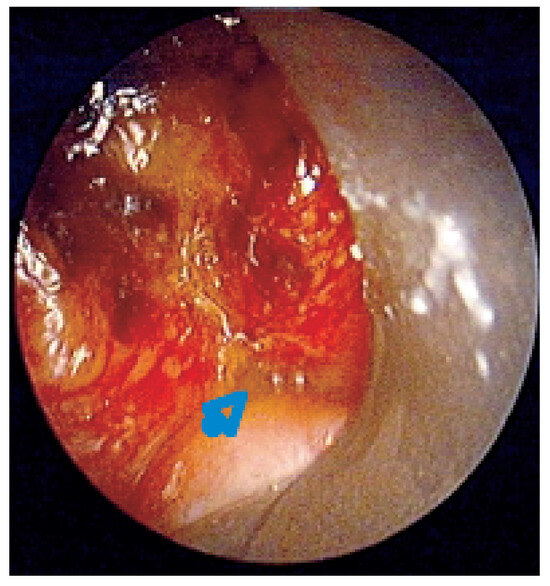

Endobronchiales Stenting

Patients with lung cancer often have bulky endobronchial disease, endobronchial extension, or airway compression. Many endobronchial treatment modalities are available to supplement traditional therapies for advanced lung cancer. Since the early 1980s, technical advances in interventional techniques have enhanced symptom-free survival and quality [...] Read more.

Patients with lung cancer often have bulky endobronchial disease, endobronchial extension, or airway compression. Many endobronchial treatment modalities are available to supplement traditional therapies for advanced lung cancer. Since the early 1980s, technical advances in interventional techniques have enhanced symptom-free survival and quality of life for patients with lung cancer. Although interventional procedures are not definitive therapies, they often relieve the strangling sensation produced by airway occlusion. For patients with respiratory symptoms associated with their disease, the stent placement provides symptom palliation and improves quality of life. The author reviews the use of several available endobronchial stents. Full article